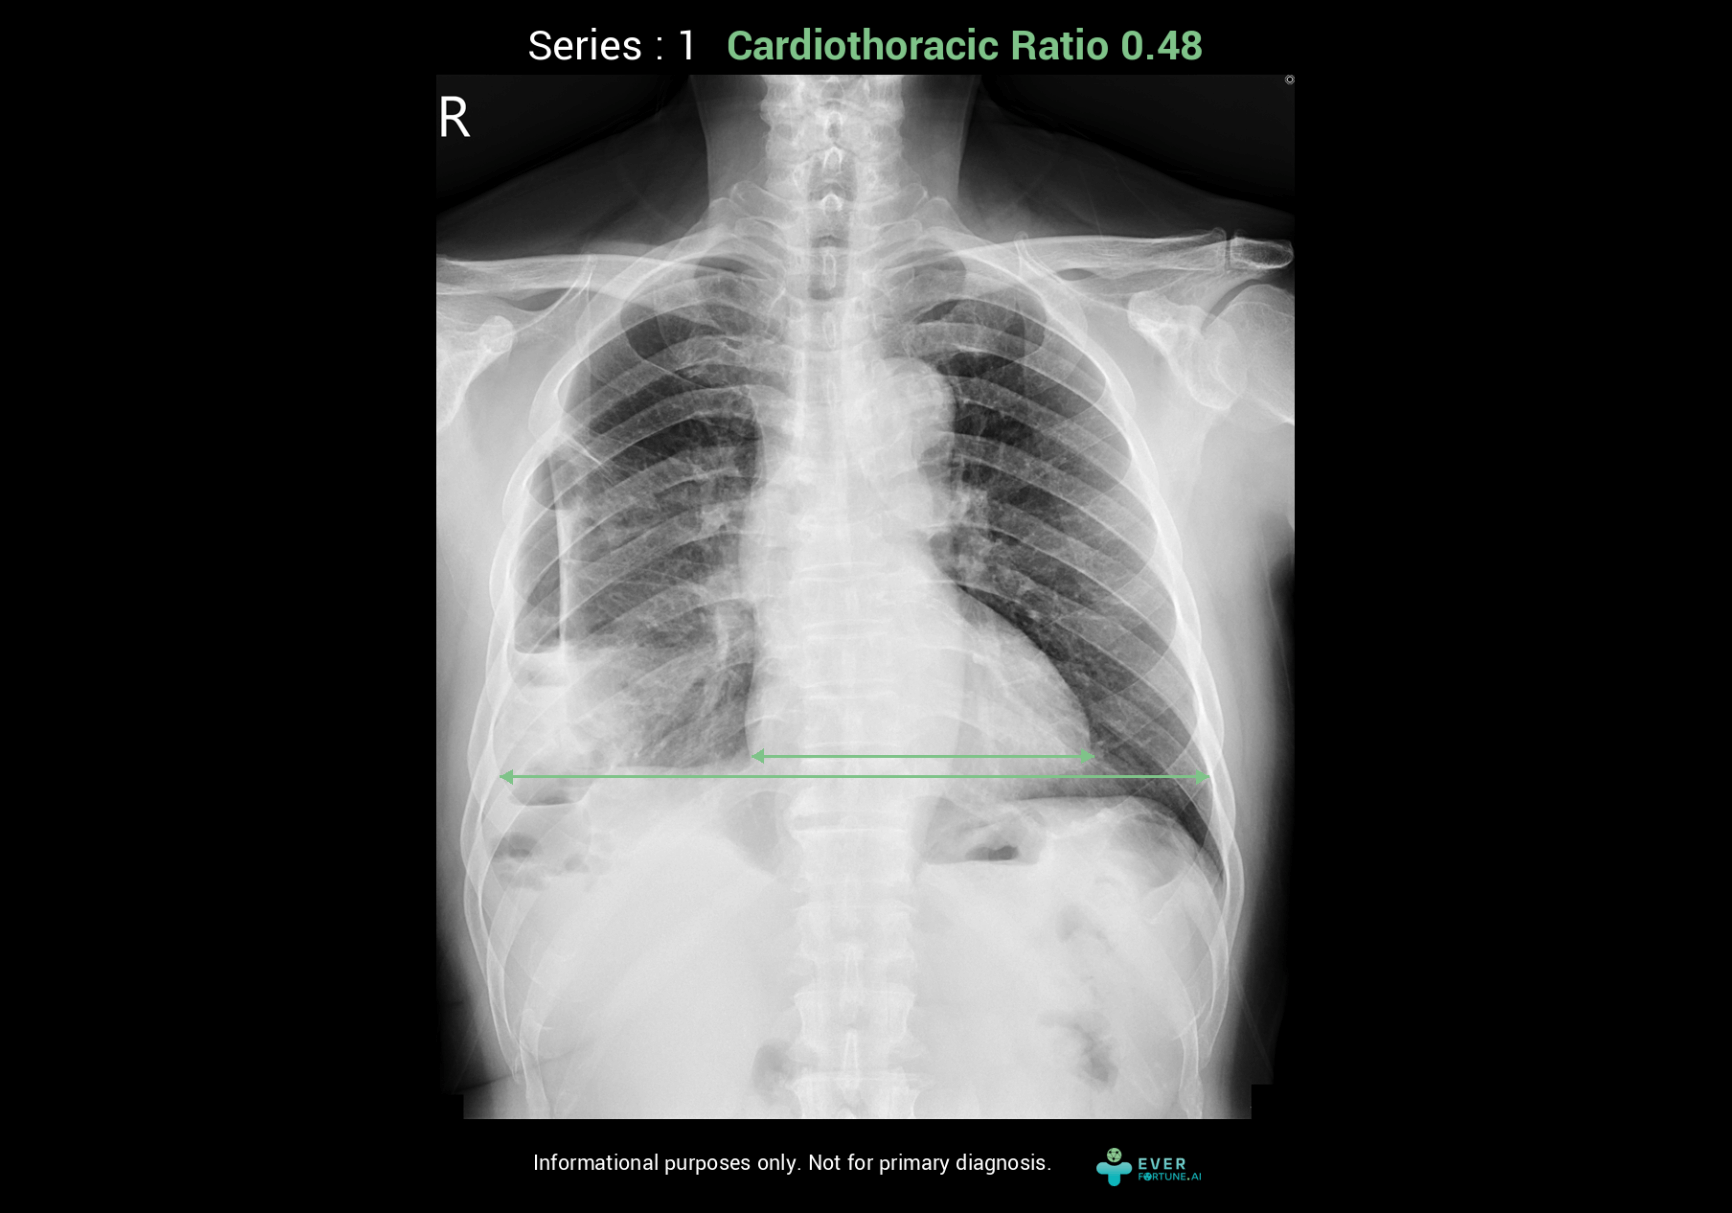

Intelligent Cardiothoracic Ratio(iCTR) Assessment System

Automatically measure the maximal transverse diameter of heart and maximal inner transverse diameter of thoracic cavity further to calculate the cardiothoracic ratio of a chest X-ray image. Enable outputting structured reports, optimizing report generation efficiency, and assisting different types of physicians in focusing more on clinical decision-making and patient care.